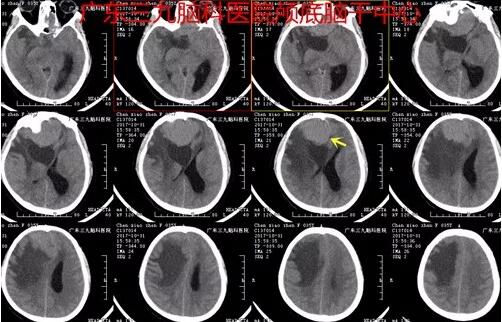

图1:2017-10-31 头颅CT示双侧额部(右侧为主)占位性病变,大小约:7.2CM×Ⅱ×5.1CM×5.5CM,呈稍高密度影